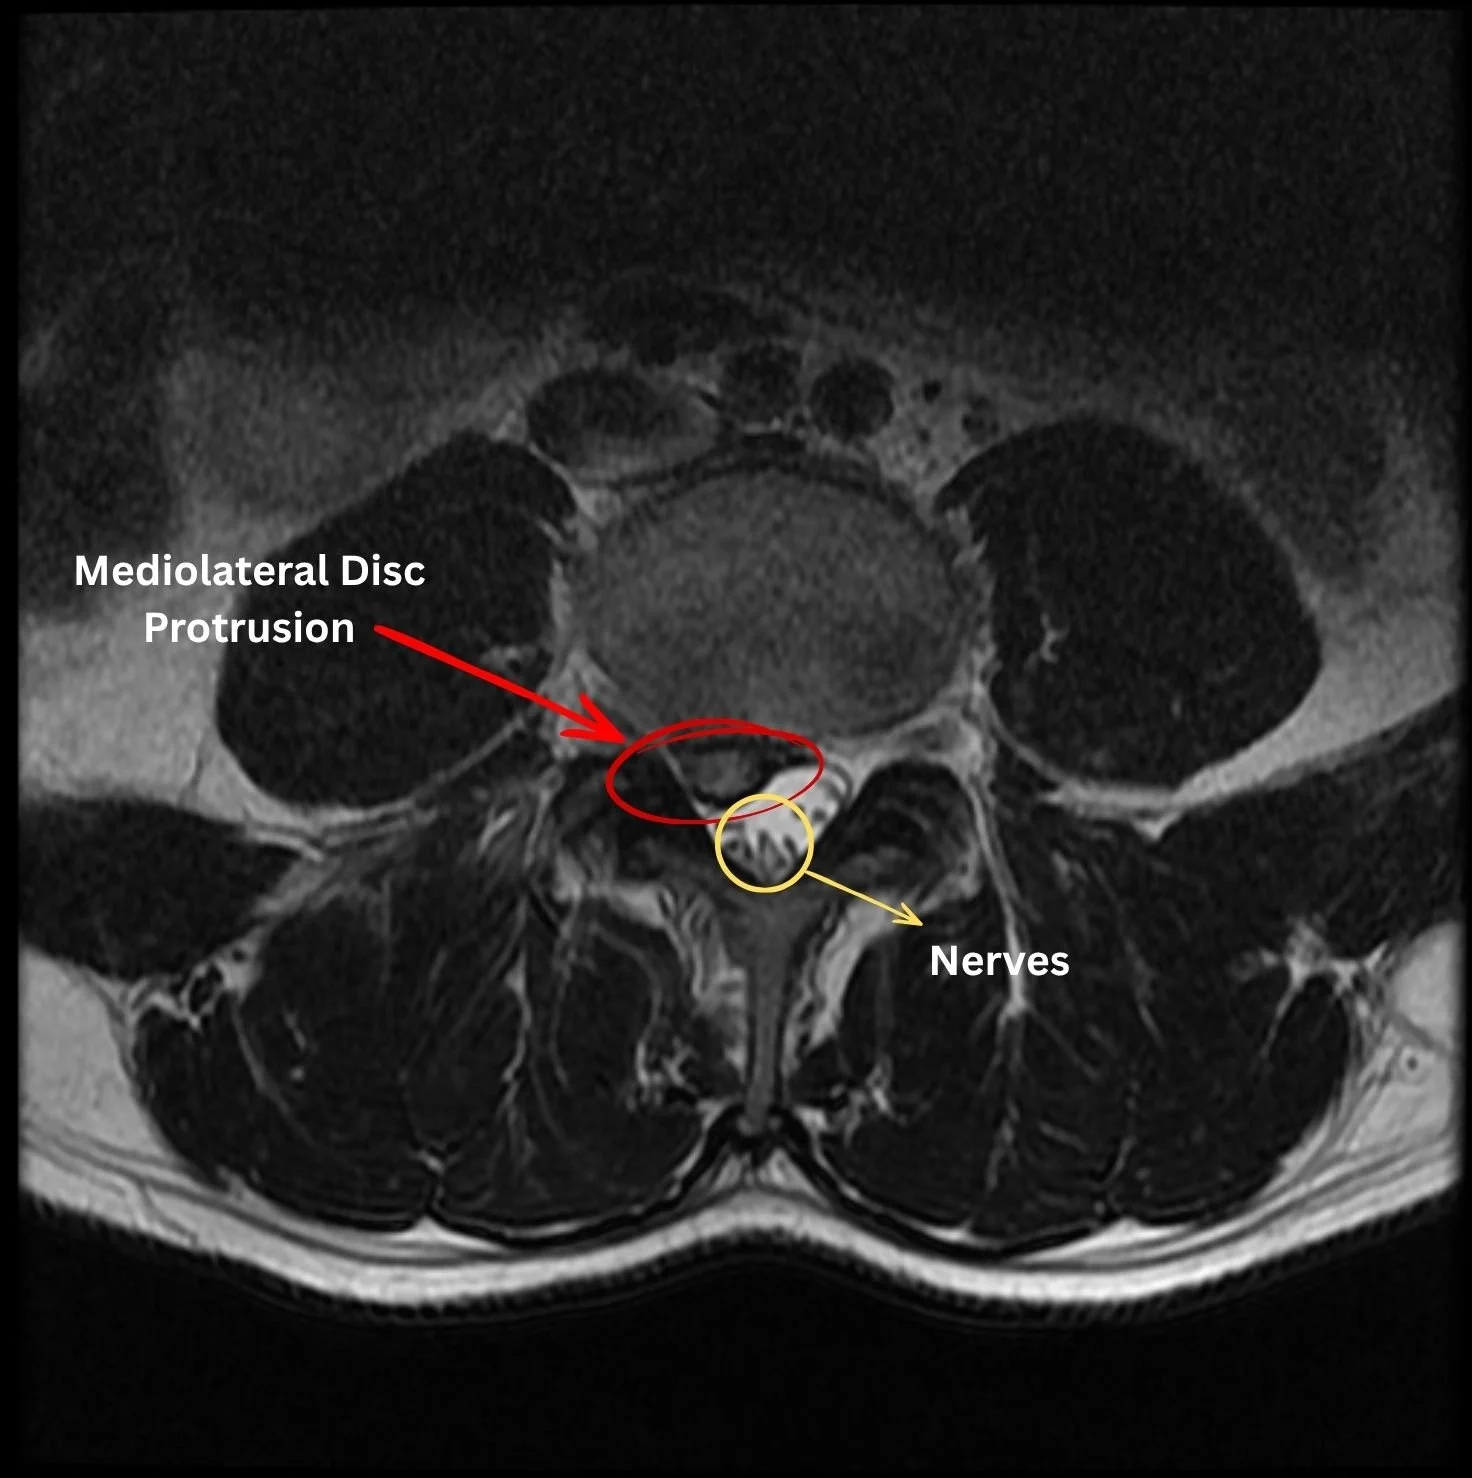

MRI of a mediolateral lumbar disc protrusion showing compression of the spinal nerves in the spinal canal.